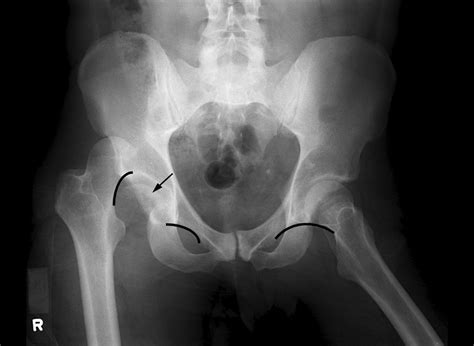

Diagnosing an impaction of fracture requires a thorough clinical evaluation and imaging studies. The diagnostic process typically involves the following steps:

• Imaging Studies: Radiographs (X-rays) are the initial imaging modality used to visualize the fracture. However, due to the complexity of impaction fractures, additional imaging studies such as computed tomography (CT) scans or magnetic resonance imaging (MRI) may be necessary to fully assess the extent of the injury.

In some cases, a CT scan may reveal the presence of bone fragments within soft tissues or other bones, providing a clearer picture of the impaction of fracture. MRI can be useful for evaluating soft tissue damage and assessing the integrity of surrounding structures.

Case Study 2: Pelvic Fracture

A 45-year-old female fell from a significant height and sustained a pelvic fracture with impaction of the bone fragments into the pelvic ring. The patient was treated with external fixation to stabilize the fracture. Post-operative rehabilitation included pain management, range of motion exercises, and functional training. The patient required additional surgical intervention for non-union and made a gradual recovery over a year.